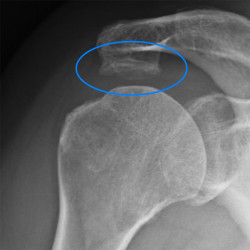

Die folgenden Röntgenbilder zeigen beispielhaft so einen Knochensporn, der die Sehne im Laufe der Jahre aufreibt:

Röntgenbilder der Schulter mit einem ausgeprägten Knochensporn: Rechts ist der Gleitraum der Rotatorenmanschette mit blau gekennzeichnet. Man kann erkennen, wie der orange eingezeichnete Sporn den Raum stark einengt.